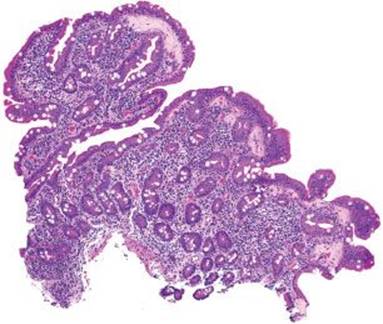

This case was received as “prominent ampulla, concerning for malignancy” (Fig. 3.313). The initial sections show duodenal mucosa with acute and chronic inflammation, gastric foveolar metaplasia, and marked reactive epithelial change (Fig. 3.313). Although these histologic features can account for a nodular clinical impression, deeper sections were pursued based on the clinical suspicion for malignancy. The first set of deeper sections were similarly concerning, but definitive malignancy was not seen. Deeper sections were repeated. And repeated. And repeated. In this case, the tissue block was exhausted and on the 38th level (!!!), clear lymphovascular invasion and infiltrating adenocarcinoma were seen (Figs. 3.314 and 3.315). When the histology does not fit the clinical scenario, consider deeper sections. When the deeper sections are not conclusive, consider repeat deeper sections or recommend rebiopsy (in this case, the patient was too unstable for a subsequent biopsy).

Figure 3.314 Infiltrating poorly-differentiated adenocarcinoma and lymphovascular space invasion. Deeper sections were performed until the block was exhausted. This photomicrograph represents the 38th (and final) section, which shows desmoplasia, infiltrating adenocarcinoma (arrowheads), and lymphovascular space invasion (asterisk). These deeper sections show an entirely different biopsy compared to the initial sections and were sufficient for chemotherapy initiation.